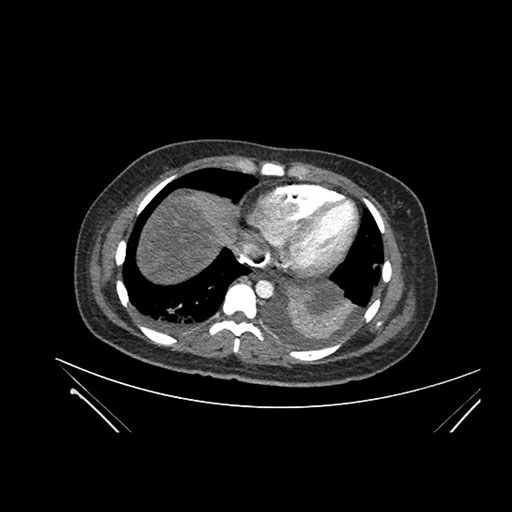

Imaging Analysis

Look through the patient's CT scan to identify any areas of concern for the necessary procedure.

Axial Venous

Based on initial findings, which issue(s) would you be most concerned about?